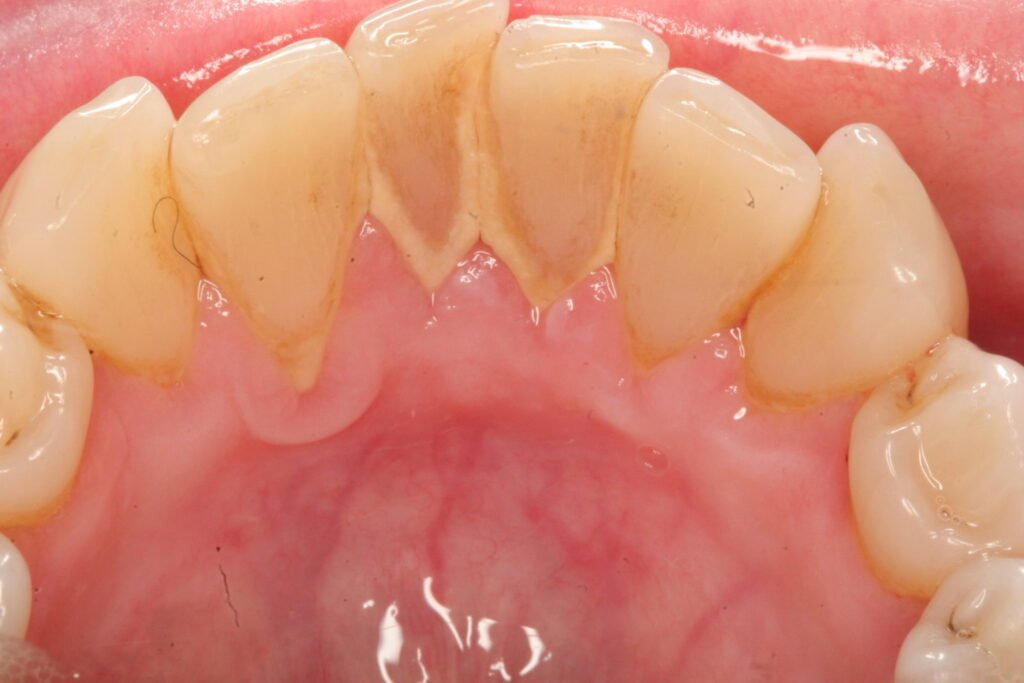

Sub-gingival

This is formed between the teeth and the gum. It’s mostly found below the gum. It’s not easily seen and can be detected using an explorer- a dental instrument. The bridge formed is dark due to the presence of black-pigmented bacteria.

Calculus can be treated using professional scaling, cleaning, debridement, or root planning. It develops below the gum-line, and special instruments are used for treating this condition. Regular dental cleaning is done if your teeth are not affected by bone loss or periodontitis. Here, the dentist uses a scaler to scrape the hardened plaque between your teeth and around your gums.

Debridement is done if you have dense calculus that prevents your dentist from performing an oral evaluation. Then, ultrasonic instruments are used to break and remove the calculus.